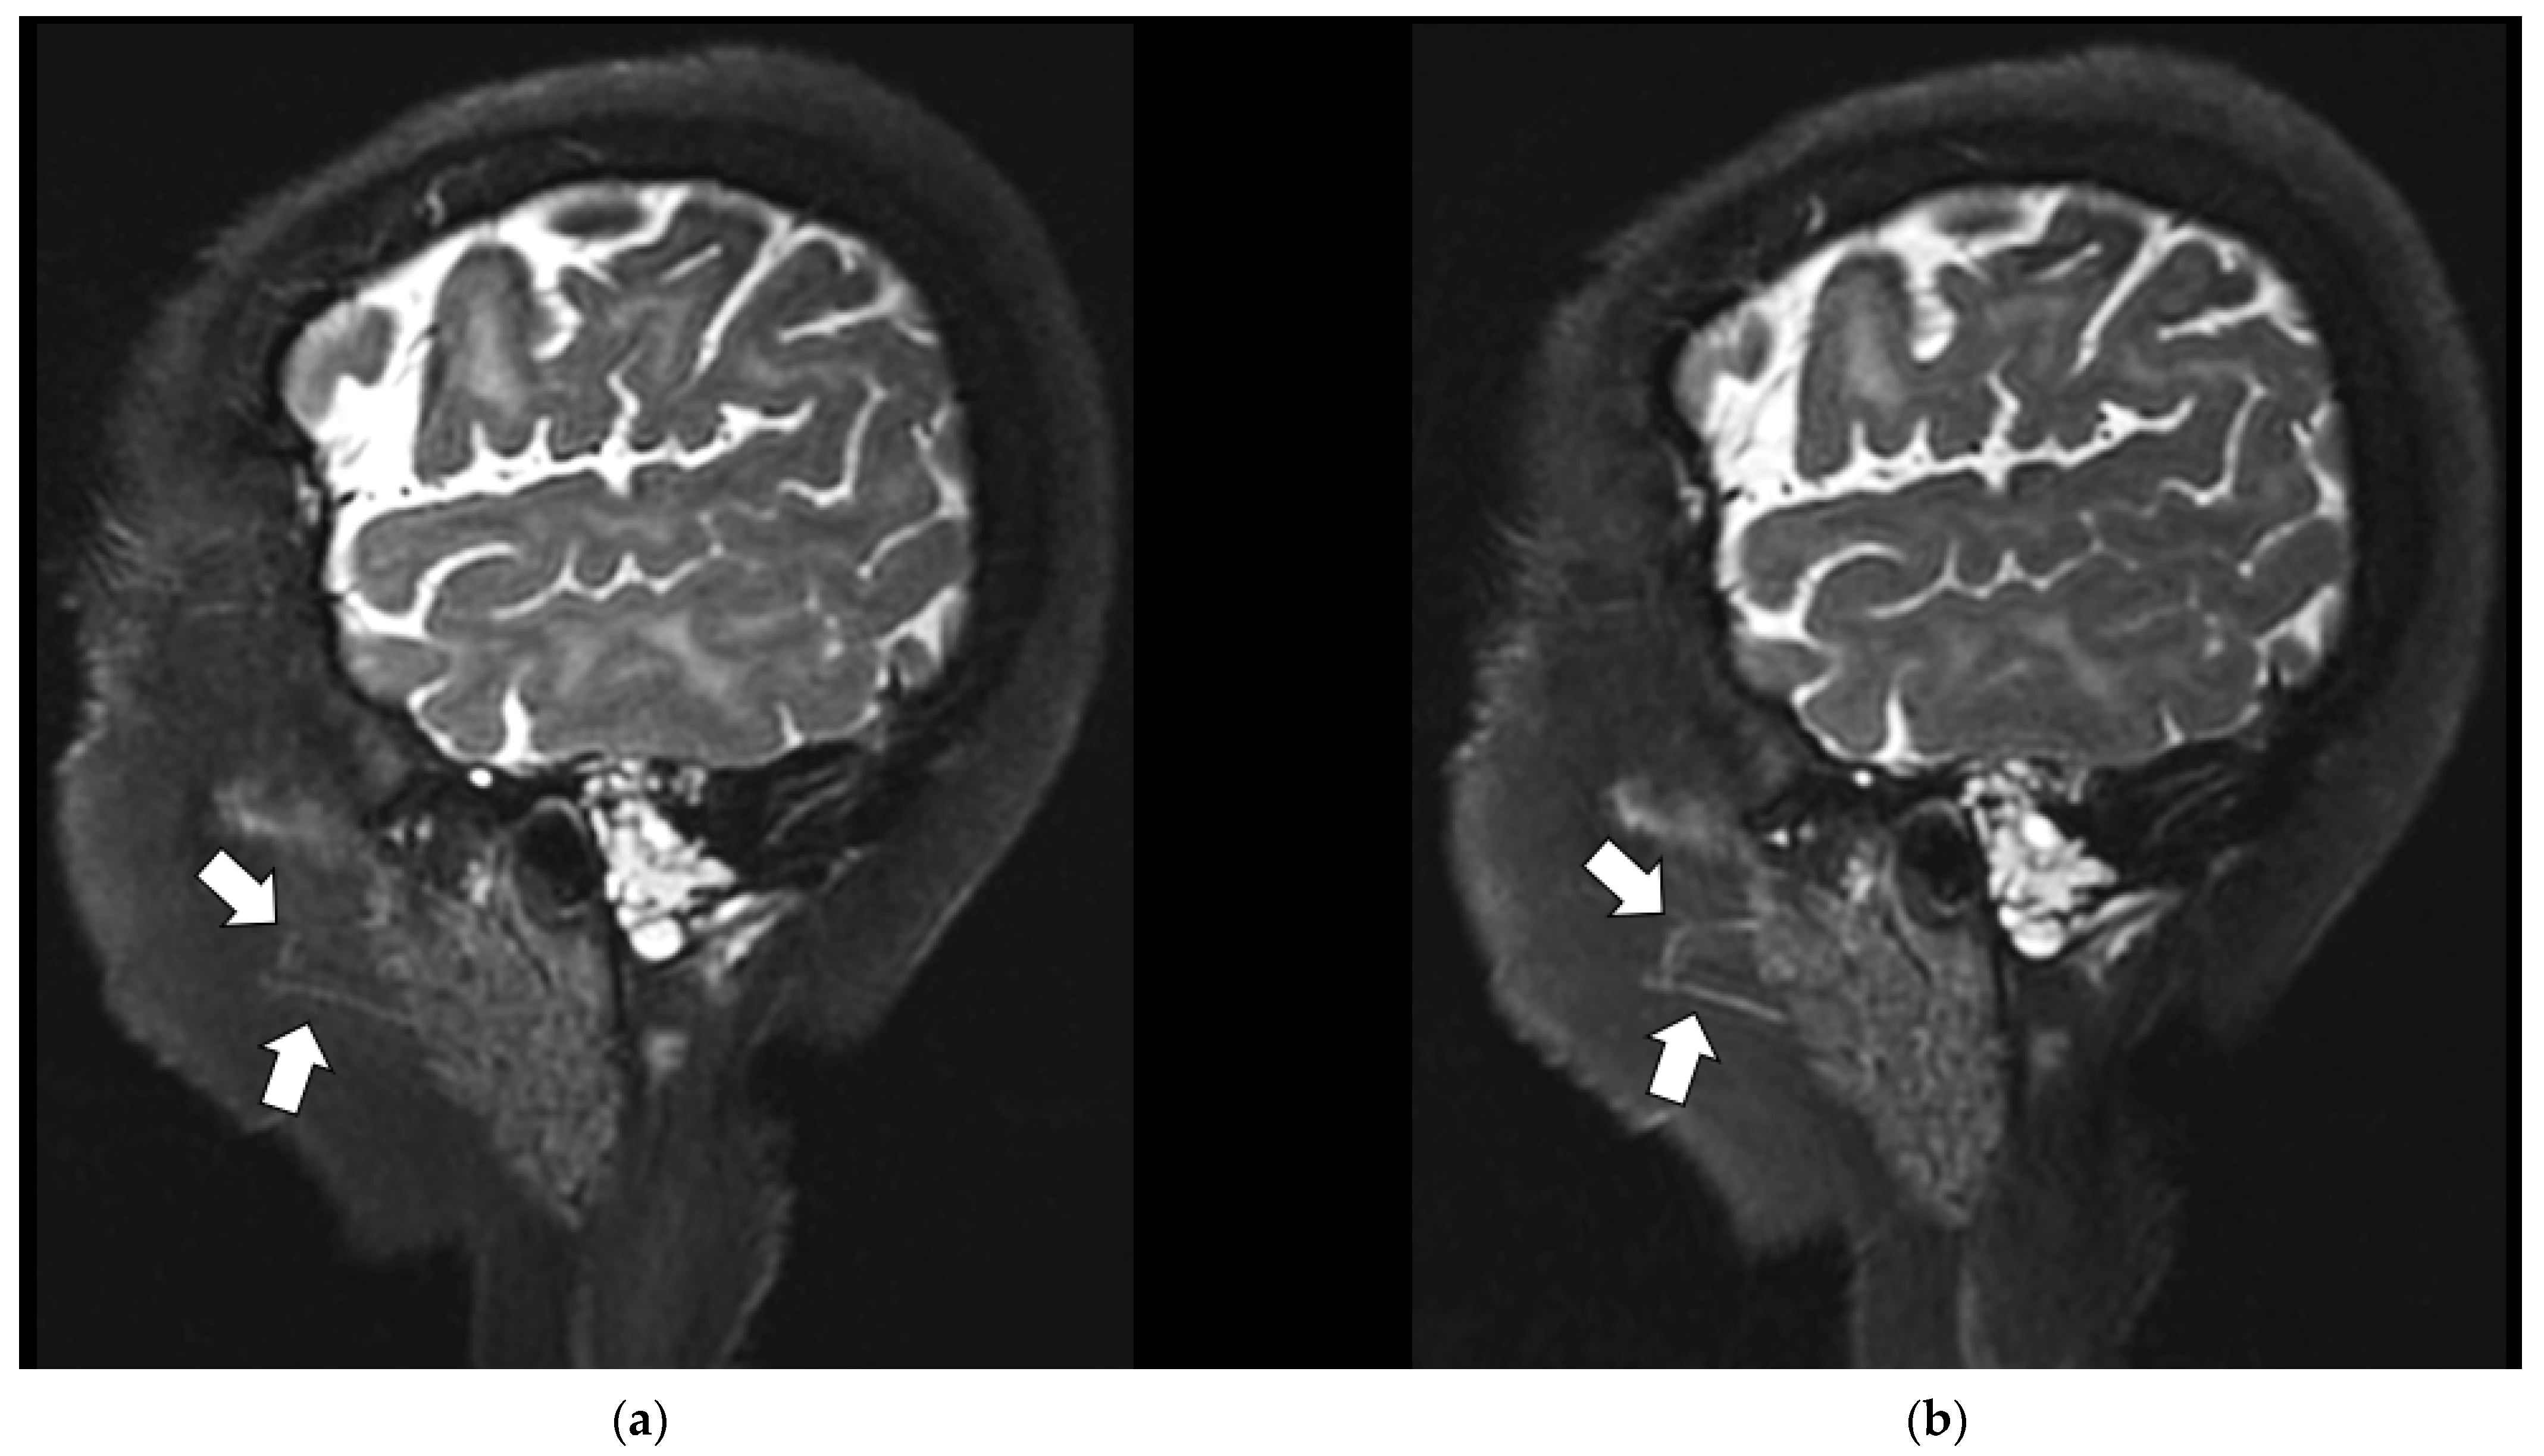

3.3.3. Coil Placement

3.3.4. SNR and Anatomic Conspicuity